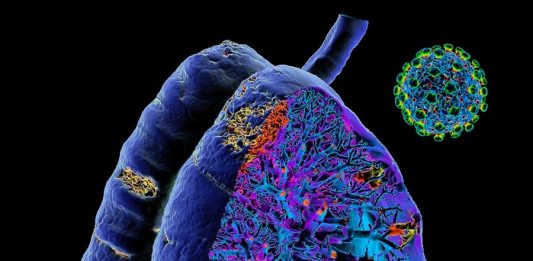

Tajne korone: Lekar objasnio šta se to događa desetog dana bolesti

Hrvatski doktor Bruno Baršić je objasnio šta se to događa desetog dana bolesti kovid-19 i zašto se obolelima tada naglo pogorša stanje, prenosi Večernji list. „Zato što je to prirodni tok bolesti kod, srećom, malog procenta bolesnika. Kada je puno zaraženih i procenat je veći. Tok bolesti ide tako da prvo počne kao običan grip. Već … Nastavi sa čitanjem Tajne korone: Lekar objasnio šta se to događa desetog dana bolesti